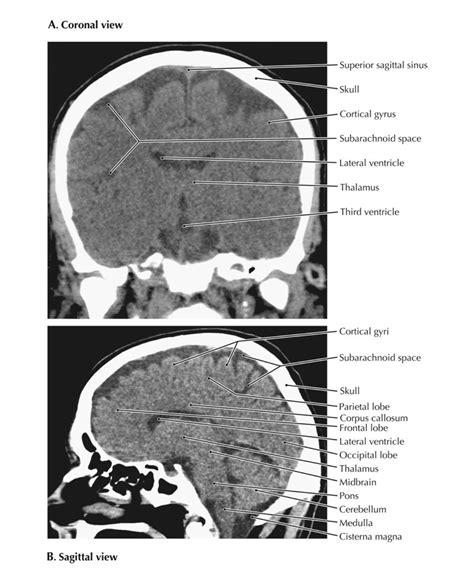

A Normal Ct Head Png serves as a benchmark for comparing abnormal scans. It helps radiologists and neurologists identify deviations from the standard anatomy, which can indicate various medical conditions. The normal scan provides a clear picture of the brain’s structure, including the ventricles, cerebral cortex, and other critical areas.

Interpreting a Normal Ct Head Png involves a thorough understanding of brain anatomy. Radiologists look for several key features:

• Ventricles: The ventricles are fluid-filled spaces in the brain. In a normal scan, they should be symmetrical and of normal size.

• Cerebral Cortex: The cerebral cortex should appear smooth and uniform, without any signs of atrophy or lesions.

• White Matter: The white matter should be intact, without any signs of demyelination or other abnormalities.

• Blood Vessels: The major blood vessels should be clearly visible and free of any blockages or aneurysms.